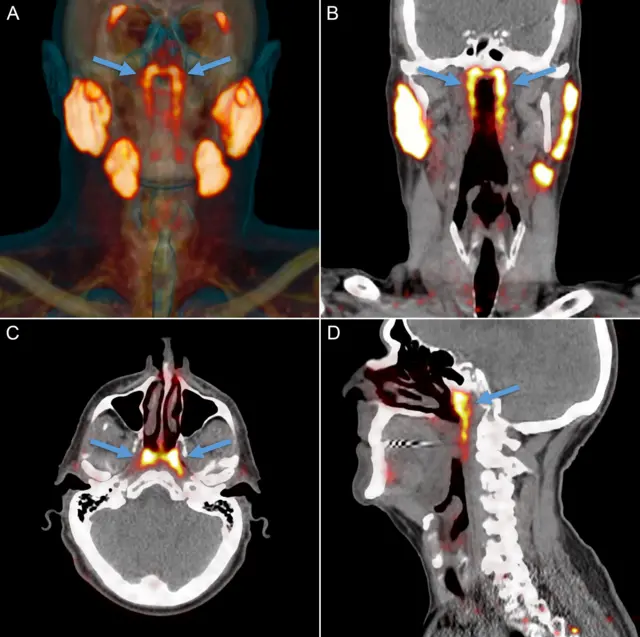

Открытие произошло случайно, в ходе обследования пациентов с раком простаты при помощи новейшего сканера PSMA PET/CT. При контрастной томографии с введением в кровь радиоактивной глюкозы этот диагностический инструмент находит в теле опухоли.

Не замеченный ранее четвертый набор слюнных желез, открытый командой Фогеля, гораздо крупнее и находится позади носа и над нёбом, в самой середине головы.

"Два органа, высветившихся при исследовании, имеют все признаки слюнных желез, - говорит ведущий автор исследования, хирург полости рта Маттейс Вальстар из Амстердамского университета.

"Мы назвали их трубчатыми железами, поскольку они расположены над трубчатым валиком [возвышение в носовой части глотки, в котором находится хрящ евстахиевой трубы].

Трубчатые железы были обнаружены у всех 100 пациентов, обследованных с помощью аппарата PSMA PET/CT. Вскрытие двух тел, мужского и женского, также подтвердило существование заметной невооруженным глазом парной структуры в виде дренажных капилляров в задней стенке носоглотки.